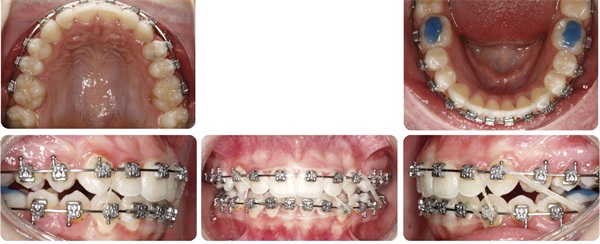

Figure 6 shows progress records midway through her treatment after braces were bonded. Bite turbos were placed posterior on the molars because I wanted to limit any vertical increase in this case as that would have the potential of further decreasing chin prominence. Posterior bite turbos used to limit molar eruption and clockwise mandibular rotation are quite important in chin-deficient patients. Upper incisor brackets were not flipped to reverse torque in this case as I desired the upper incisors to roll forward a bit like we discussed earlier. Approximately 0.3 mm of IPR was performed at each contact canine to canine in both arches.

Figure 7 shows final records as treatment finished in 24 months. Notice in Figures 8 and 9 that the upper incisors rolled forward to a more ideal labiolingual inclination during this treatment.

Figure 12 shows that the lower incisors also rolled forward within her thick alveolar housing to couple with this more forward position of her maxillary incisors (pre-tx on the inside, post-tx on the outside). If she had a thinner type of housing, it might have impacted my tolerance for this movement.

The Architects of the Lips: Part 4

Fig. 12

There are obviously many ways to treat this case and I don’t present my way as the best or only way to treat Rylee. Her orthodontic treatment could have been done well without advancing her upper incisors or even by way of extracting permanent teeth. Treatment goals set the course and those vary greatly. For me, it started by looking outside-in and appreciating her lips and what was possible to enhance their presentation, noticing a deficiency in the aesthetic A-P projection of her upper incisors in her smile, and then visualizing her mandibular housing via CBCT to assess how this occlusal change might be tolerated.